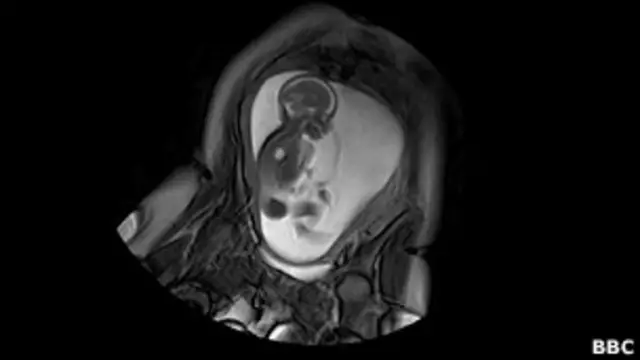

Cientistas britânicos deram início a um projeto de seis anos para mapear as conexões nervosas desenvolvidas no cérebro de um bebê ainda no útero e imediatamente após o nascimento.

Pesquisadores do Guy's and St Thomas' Hospital, do King's College de Londres, do Imperial College e da Universidade de Oxford querem produzir um diagrama que mostre como o cérebro cresce, a um nível de detalhe que dizem ter sido impossível de se obter até agora.

Imagens do cérebro são cortesia do Centre for the Developing Brain, do King's College de Londres.